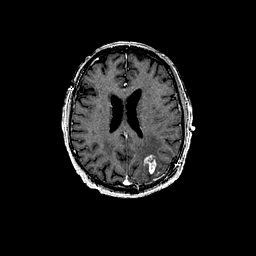

Glioma overlay -- Slice #73

[Home][Help][Clinical] Slice 73